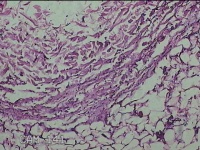

右后颈部包块

性别

女

年龄

31岁

临床诊断

头颈皮脂腺囊肿

一般病史

发现后颈部包块1年余。

标本名称

大体所见

灰白粉红色包块2.3x1.5x0.8cm一个,表面光滑,带少许脂肪,部分已切开,切面灰白粉红色,质中。

图2

制片质量、图片信息影响判读。